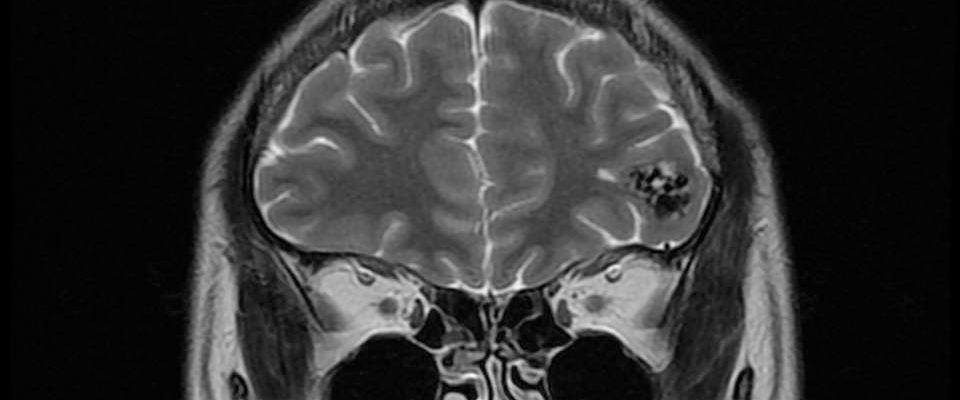

病人….被另一名曾經嚴重腦出血性中風(腦動脈瘤破裂以致嚴重的蜘蛛綱膜下腔出血及曾經瞳孔放大和深度昏迷…其後完全康復)的病人介紹…..帶MRI 底片到我診所尋求第二醫療諮詢….. 其時心情亦愉快…….直到….看了MRI 影像後…..我告訴她真正的MRI檢查結果……她的左前腦額葉上….有一個3cm大的腦動靜脈畸形血管瘤(AVM).. ….亦有最近出過血的跡象…可能是她失去意識和腦癇症的原因。

兩天後….在私家醫院為她做診斷式的動態腦血管造影來確定䐉血液的流動模式後,再進行了4 小時的顯微鏡手術….AVM的計時炸彈完全切除……..在AVM旁邊的腦部亦能看到血鐵黃素的舊有殘留血液。手術後兩天出院。